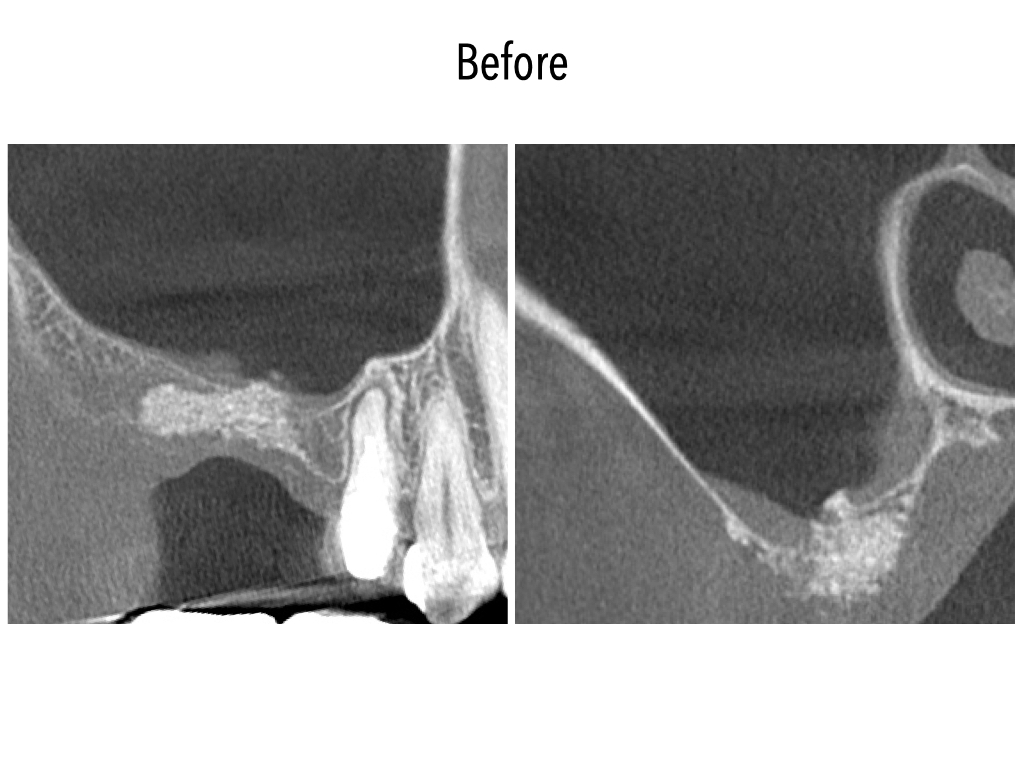

サイナスリフトとは、上あごの骨の高さが足りずインプラント治療が難しい場合に、上あごの奥にある「上顎洞(じょうがくどう)」と呼ばれる空洞の底を持ち上げて骨を造成する手術です。手術でできた空間に骨補填材などを充填し、骨が再生・定着するのを待ってからインプラントを埋め込みます。

骨の厚みが大きく不足している場合にもインプラント治療が可能になります。

| 治療内容 | 右側サイナスリフト |